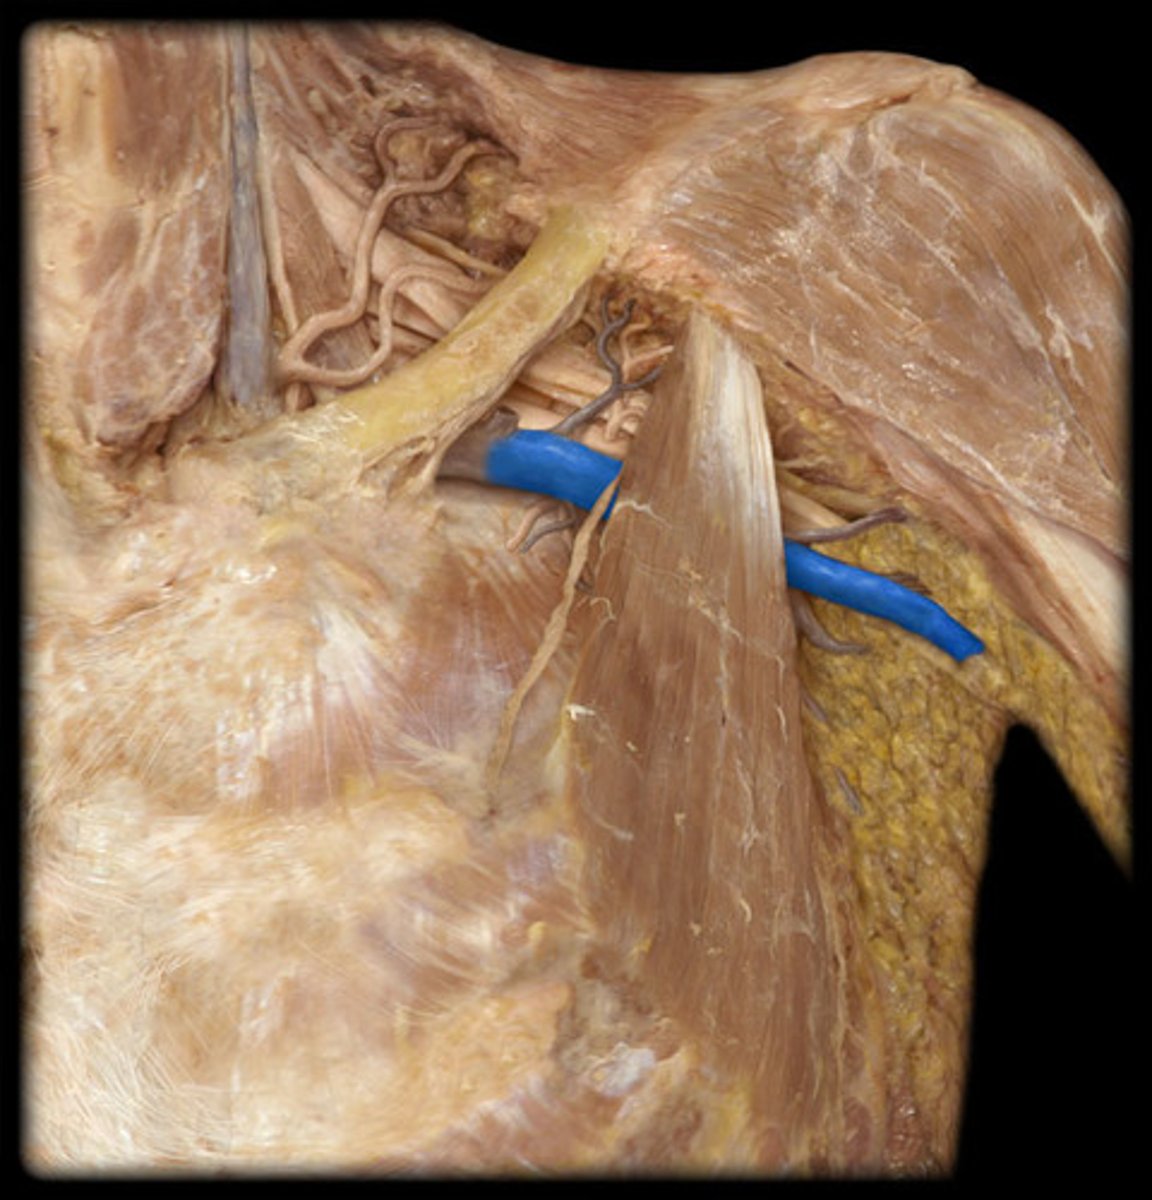

Axillary v.

pertaining to the armpit

Axillary n.

pertaining to the armpit or underarm